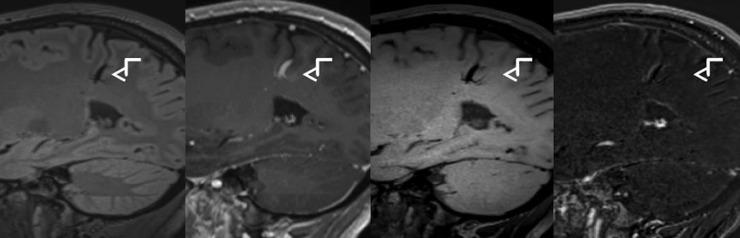

In multiple sclerosis (MS) the sensitivity for detection of contrast enhancing lesions (CEL) in T1-weighted scans is essential for diagnostics and therapy decisions. The purpose of our study was to evaluate the sensitivity of T1w MPRAGE scans in comparison to T1w dark blood technique (T1-DB) for CEL in MS.

MATERIALS AND METHODS

3T MR imaging was performed in 37 MS patients, including T2-weighted imaging, T1w MPRAGE before and after gadolinium injection (unenhanced-T1 and T1-CE) and T1-DB imaging. After gadolinium application, the T1-DB scan was performed prior to T1-CE. From unenhanced-T1 and T1-CE scans, subtraction images (T1-SUB) were calculated. The number of CEL was determined separately on T1-CE and T1-DB by two raters independently. Lesions only detected on T1-DB scans then were verified on T1-SUB. Only lesions detected by both raters were included in further analysis.

RESULTS

In 16 patients, at least one CEL was detected by both rater, either on T1-CE or T1-DB. All lesions that were detected on T1-CE were also detected on T1-DB images. The total number of contrast enhancing lesions detected on T1-DB images (n = 54) by both raters was significantly higher than the corresponding number of lesions identified on T1-CE (n = 27) (p = 0.01); all of these lesions could be verified on SUB images. In 21 patients, no CEL was detected in any of the sequences.

CONCLUSIONS

The application of T1-DB technique increases the sensitivity for CEL in MS, especially for those lesions that show only subtle increase in intensity after Gadolinium application but remain hypo- or iso-intense to surrounding tissue.

在多发性硬化症(MS)中,T1加权扫描中检测对比增强病灶(CEL)的敏感性对于诊断和治疗决策至关重要。我们研究的目的是评估T1加权MPRAGE扫描与T1加权黑血技术(T1-DB)相比对MS中CEL的敏感性。

材料与方法

对37例MS患者进行3T磁共振成像,包括T2加权成像、钆注射前后的T1加权MPRAGE(未增强T1和T1-CE)以及T1-DB成像。应用钆后,在T1-CE之前进行T1-DB扫描。从未增强T1和T1-CE扫描中计算减法图像(T1-SUB)。两名评估者分别在T1-CE和T1-DB上确定CEL的数量。然后在T1-SUB上验证仅在T1-DB扫描中检测到的病灶。仅两名评估者均检测到的病灶纳入进一步分析。

结果

在16例患者中,两名评估者在T1-CE或T1-DB上均检测到至少一个CEL。在T1-CE上检测到的所有病灶在T1-DB图像上也被检测到。两名评估者在T1-DB图像上检测到的对比增强病灶总数(n = 54)显著高于在T1-CE上识别的相应病灶数(n = 27)(p = 0.01);所有这些病灶均可在SUB图像上得到验证。在21例患者中,任何序列均未检测到CEL。

结论

T1-DB技术的应用提高了MS中CEL的敏感性,特别是对于那些在应用钆后强度仅轻微增加但对周围组织仍呈低或等强度的病灶。